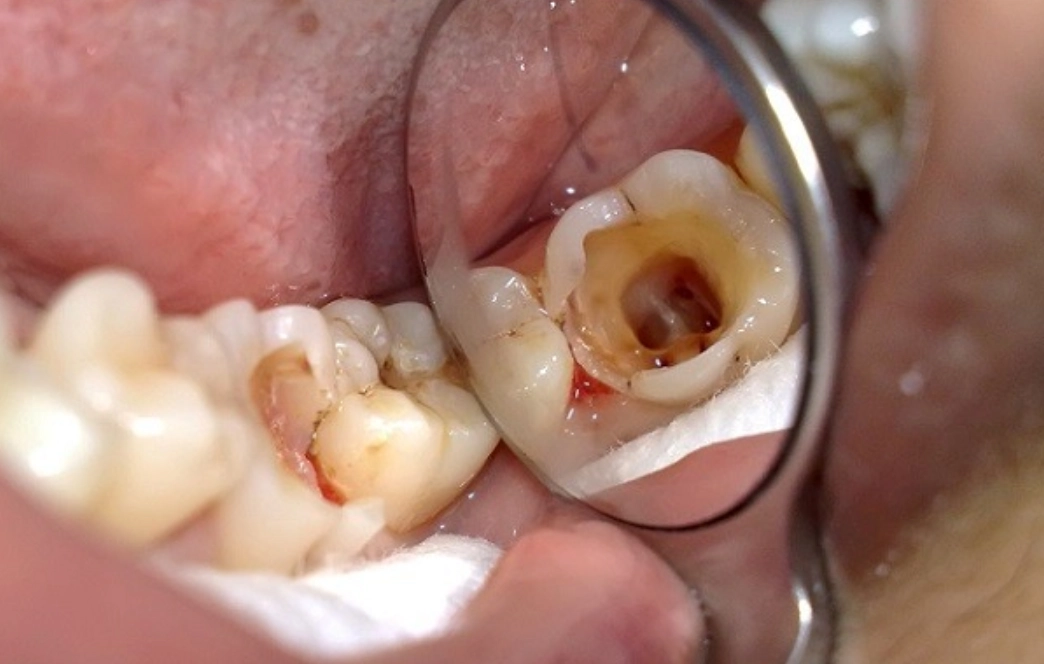

3.1. Dấu hiệu cho thấy tủy răng đang “kêu cứu”:

- Răng vỡ lớn do sâu hoặc chấn thương làm lộ tủy

- Thăm khám, chẩn đoán chính xác: Bác sĩ thăm khám kỹ lưỡng, chụp X-quang hoặc CT Cone Beam để xác định tình trạng tủy răng và lên kế hoạch điều trị chi tiết.

- Trải nghiệm nhẹ nhàng: Kỹ thuật gây tê hiện đại và công nghệ nội nha tiên tiến (máy nội nha quay, định vị chóp) giúp quá trình điều trị chính xác, hiệu quả và không đau.

- Trám bít ống tủy và phục hồi răng: Sau khi làm sạch, ống tủy được trám bít kín bằng vật liệu chuyên dụng. Bọc răng sứ là giải pháp tối ưu để bảo vệ răng khỏi nứt vỡ và khôi phục chức năng, thẩm mỹ.